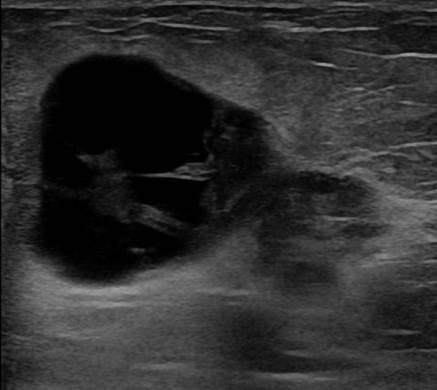

Ung thư vú

» Thông tin: Nữ giới – 55 tuổi.

» Lâm sàng: Khối tuyến vú.